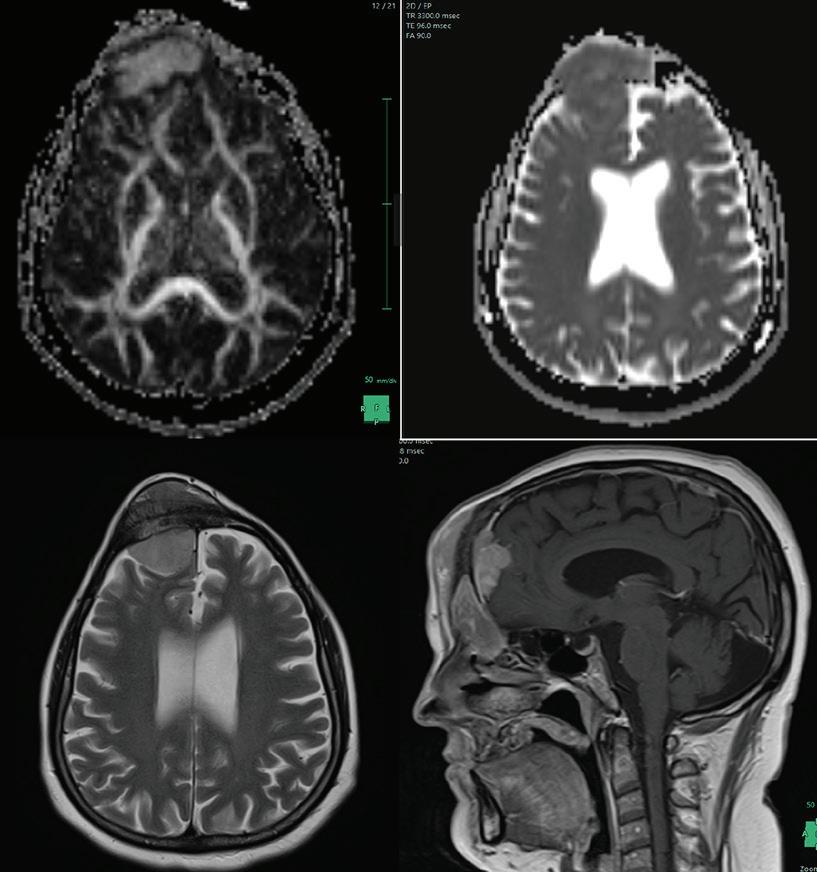

Figura 2. Se utilizó secuencias de pulso para T1, T2 y FLAIR y T1 tras la administración de contraste paramagnético. Se observa a nivel frontal, lesión sólida, extra-axial, que se extiende hacia ambos lados de la bóveda craneal, es ligeramente hiperintensa con respecto al parénquima encefálico en secuencias T1 y T2, se extiende al seno frontal y hacia las partes blandas adyacente a ese Intenso realce tras la administración de contraste endovenoso, evidenciándose adherencia dural.

Figura 1. En el examen físico se observa tumoración frontal bilateral a predominio lado derecho. Hospital de Clínicas “Jose de San Martín”, 2021 Figura 2